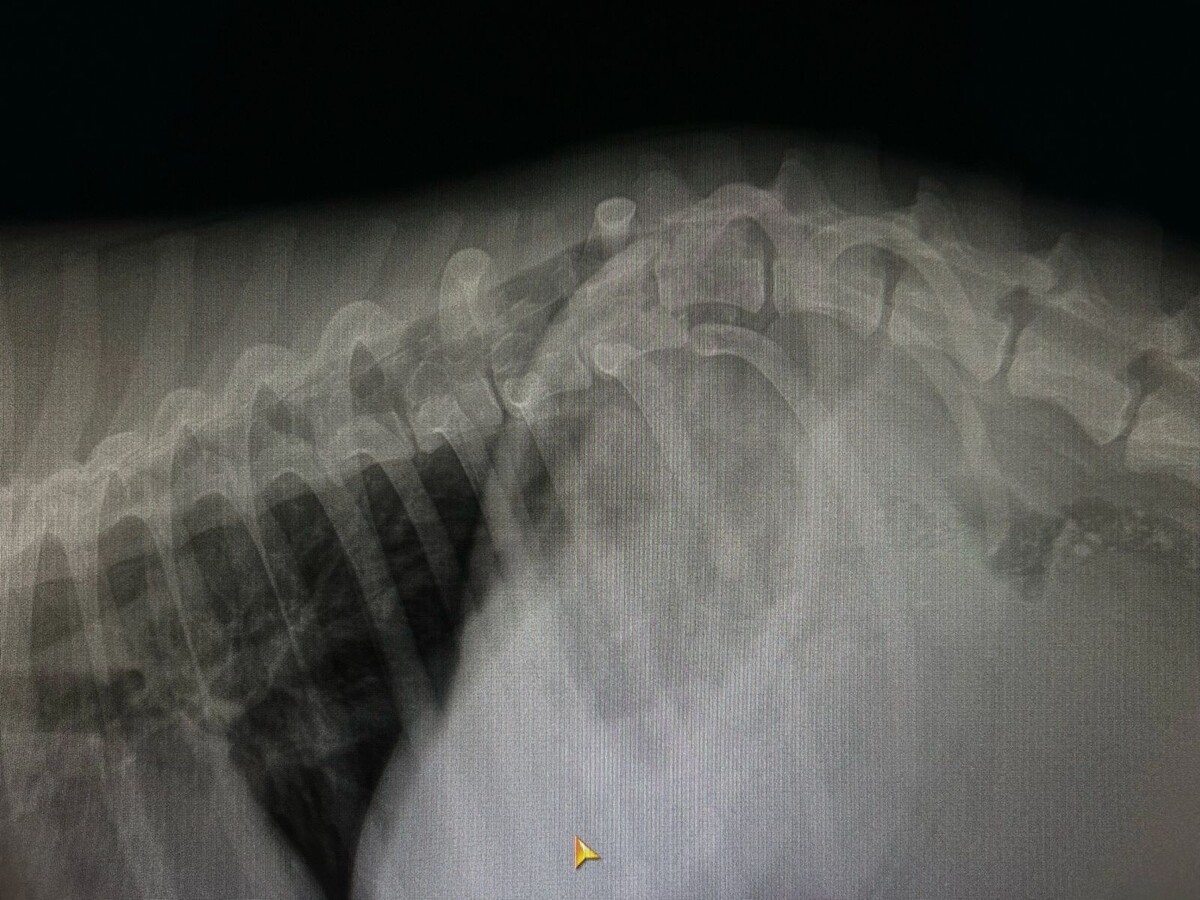

Собаку доставили в клинику. Сделали рентген.

Разрыв позвоночника. Собака (девочка) спинальница.

Внутренних повреждений не обнаружено.